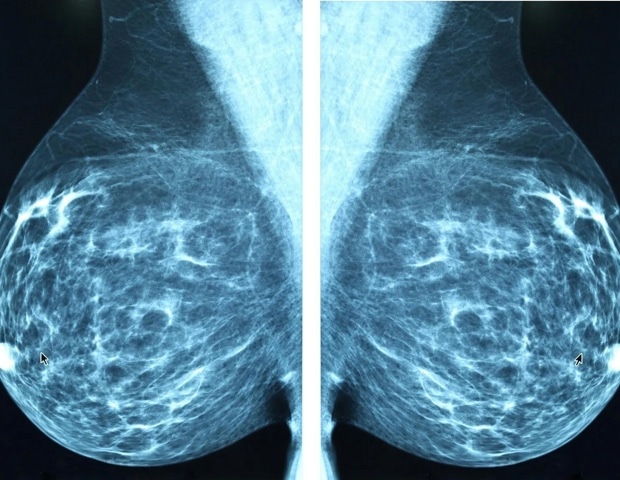

Une protéine naturelle qui a tendance à être exprimée à des niveaux plus élevés dans les cellules cancéreuses du sein renforce l’efficacité de certains agents anticancéreux, notamment la doxorubicine, l’une des chimiothérapies les plus largement utilisées, et un médicament préclinique connu sous le nom d’ErSO, rapportent les chercheurs. La protéine FGD3 contribue à la rupture des cellules cancéreuses perturbées par ces médicaments, renforçant ainsi leur efficacité et renforçant les immunothérapies anticancéreuses.

La découverte est décrite dans le Journal of Experimental & Clinical Cancer Research.

Les nouvelles découvertes sont le résultat heureux d’expériences impliquant ErSO, un médicament expérimental qui a tué 95 à 100 % des cellules cancéreuses du sein positives aux récepteurs d’œstrogènes dans un modèle murin de la maladie. ErSO régule positivement une voie cellulaire qui protège normalement les cellules cancéreuses du stress, a déclaré David Shapiro, professeur de biochimie à Urbana-Champaign de l’Université de l’Illinois, qui a dirigé les nouveaux travaux avec Junyao Zhu, étudiant diplômé de l’Illinois. Mais lorsque cette voie de protection s’intensifie, le système tourne mal.

« La plupart des médicaments anticancéreux inhibent quelque chose dont la cellule a besoin pour survivre, et soit ils empêchent la cellule de se développer, soit, dans certains cas, la font mourir d’une manière ordonnée appelée apoptose », a déclaré Shapiro. « Mais ErSO fait exactement le contraire. Il suractive la voie cellulaire et les cellules cancéreuses gonflent et se déchirent littéralement. »

Shapiro et Paul Hergenrother, professeur de chimie à l’Université d’I., ont découvert ErSO pour la première fois et en ont fait rapport en 2021. Dans la nouvelle étude, ils voulaient mieux comprendre le fonctionnement d’ErSO en identifiant les protéines cellulaires qui jouent un rôle dans « la prise de décisions de vie ou de mort pour les cellules », a déclaré Shapiro.

Pour ce faire, ils ont testé le médicament contre des lignées cellulaires du cancer du sein, dont chacune avait un de ses 18 000 gènes supprimé. Si un gène supprimé fragilise l’efficacité de un médicament – dans ce cas ErSO – c’était un signal que ce gène jouait un rôle dans la voie de destruction du cancer par le médicament.

« La principale cible du criblage avec ErSO était le gène de cette protéine peu étudiée appelée FGD3 », a déclaré Shapiro.

Ainsi, nous avons manipulé les niveaux de FGD3 dans les cellules cancéreuses et avons constaté qu’il contrôlait effectivement si ErSO pouvait tuer les cellules. Et dans une série d’expériences importantes, Zhu a montré que FGD3 affaiblit l’architecture cellulaire. »

Lorsqu’il n’est pas attaqué par une chimiothérapie ou d’autres thérapies anticancéreuses, le FGD3 rend les cellules cancéreuses plus flexibles, leur permettant de se déplacer et de changer de forme, facilitant leur migration et augmentant probablement leur potentiel de métastases, ont indiqué les chercheurs. Mais lorsqu’un médicament comme ErSO ou la doxorubicine perturbe les cellules cancéreuses, FGD3 provoque la rupture des cellules cancéreuses enflées.

Cette rupture libère le contenu de la cellule, alertant le système immunitaire du corps, qui envoie des cellules tueuses naturelles et des macrophages pour terminer le travail, a déclaré Shapiro.

Les expériences ont été menées sur des cultures cellulaires 2D et sur des « organoïdes dérivés de patients atteints d’un cancer du sein » 3D, qui imitent plus fidèlement l’environnement de la tumeur, a déclaré Shapiro. Le co-auteur de l’étude, le Dr Olufunmilayo Olopade, directeur du Centre de génétique clinique du cancer et de santé mondiale à l’Université de médecine de Chicago, a développé les organoïdes.

« Les travaux d’un certain nombre de laboratoires ont montré que ces organoïdes peuvent conserver le même schéma de production de protéines que celui qui se produit dans la tumeur d’origine », a déclaré Shapiro.

L’équipe a également testé le rôle de FGD3 dans un modèle murin de cancer du sein humain, et a découvert le même schéma : des niveaux plus élevés de FGD3 ont amélioré le pouvoir destructeur d’ErSO.

« L’une des choses que nous avons constatées est que FGD3 a considérablement augmenté le mouvement vers la membrane des cellules cancéreuses d’une protéine qui stimule les cellules tueuses naturelles pour cibler une cellule cancéreuse en vue de sa destruction », a déclaré Shapiro. « Cela a le potentiel d’améliorer immunothérapie contre le cancer et pour réduire les doses de médicaments toxiques que vous devez utiliser. Ceci est particulièrement important dans le cancer du sein, car l’immunothérapie a eu un succès limité contre les tumeurs solides telles que le cancer du sein. »

L’équipe de recherche a également analysé une vaste quantité de données sur le cancer du sein humain, à la recherche de tendances entre les niveaux de FGD3 et les réponses à divers agents de chimiothérapie.

« Nous avons constaté, avec tous les types de chimiothérapie et toutes les classes de cancer du sein, qu’il existe une très forte corrélation entre le niveau de FGD3 et la réponse favorable de la patiente à la chimiothérapie », a déclaré Shapiro. « Ceux avec un niveau élevé sont très réactifs ; ceux avec un faible niveau sont peu réactifs. Cela nous permettra d’identifier les patients les plus susceptibles de bénéficier de ces types de thérapies contre le cancer. »